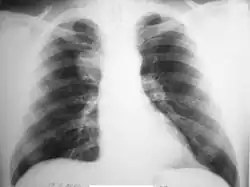

На рентгенограммах гамартомы с внутрилёгочной локализацией имеют вид одиночных (гораздо реже — множественных) шаровидных теней (солитарных лёгочных узлов) с чёткими, слегка волнистыми контурами[19]; при дольчатом строении очертания опухоли могут быть бугристыми. Характерны известковые включения, расположенные в виде отдельных зёрен или же в виде центрального конгломерата. Часто интенсивность тени центральной части опухоли значительно выше, чем краевых отделов (отличительная особенность гамартомы от других опухолей). Лёгочный рисунок вокруг гамартомы, как правило, не изменён[24]. Иногда имеется ободок по периферии (ложе опухоли). Характерно отсутствие изменений в корне лёгкого и плевральных реакций. При длительном динамическом наблюдении размеры гамартомы изменяются крайне медленно, но часто прогрессирует интенсивность известковых отложений[6][20].

В связи с особенностями рентгенологических проявлений выделяют 4 варианта гамартом:

- Гамартомы с неправильной, шаровидной или овальной формой, чёткими гладкими или же бугристыми контурами, имеющие весьма высокую интенсивность тени, которая уменьшается к периферии гамартомы. Характерны хорошо видимые на прямых и боковых рентгенограммах точечные, пятнистые и линейные обызвествления, которые сливаются в единый конгломерат.

- Гамартомы средней интенсивности, имеющие резко очерченные гладкие или бугристые контуры и хаотичное отложение глыбок извести в толще опухоли.

- Гамартомы с единичными или множественными очагами обызвествления, располагающимися как в толще гамартомы, так и по её периферии.

- Гамартомы без обызвествления[6].

Эндобронхиальные гамартомы проявляются прямыми (сферическое опухолевидное образование в просвете бронха с ровными и чёткими контурами при рентгеновской томографии) и косвенными признаками (различные рентгенологические проявления нарушений бронхиальной проходимости: гиповентиляция, ателектаз или вздутие, маятникообразные смещения средостения, вторичные бронхоэктазы)[2][23][26][27].